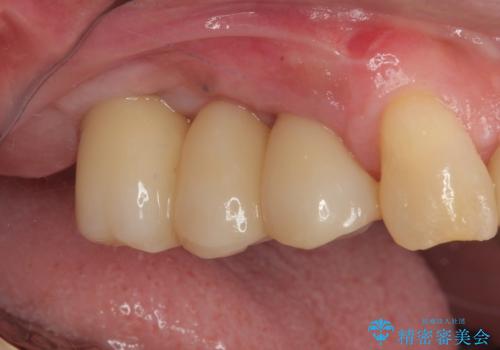

抜歯即時埋入インプラントによる補綴治療の特徴は、短期間であることや処置数が少ないことが挙げられます。また、表側の歯肉の陥凹を避けることができるというメリットがあります。しかしながら、今回は歯根破折の程度が酷く、やや膨らみを失うこととなりましたが、スムーズに治療を終えることができました。